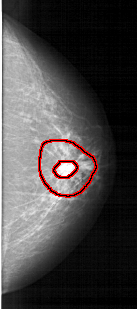

RIGHT_CC LINES 5251 PIXELS_PER_LINE 2326 BITS_PER_PIXEL 12 RESOLUTION 43.5 OVERLAY

FILE: A_1252_1.RIGHT_CC.OVERLAY

TOTAL_ABNORMALITIES 1

ABNORMALITY 1

LESION_TYPE CALCIFICATION TYPE PLEOMORPHIC DISTRIBUTION CLUSTERED

LESION_TYPE MASS SHAPE IRREGULAR MARGINS SPICULATED

ASSESSMENT 5

SUBTLETY 4

PATHOLOGY MALIGNANT

TOTAL_OUTLINES 2

BOUNDARY

CORE